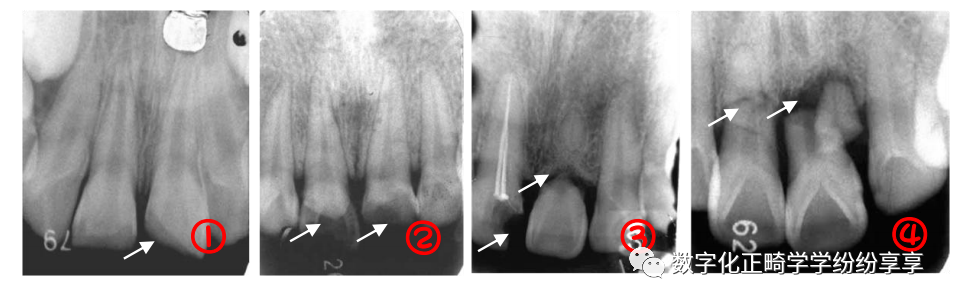

牙周病 Periodontitis:

牙槽骨水平型吸收

曲面断层片怎么看正畸【曲面断层片(全景片)】如何解读和查看:牙周?牙体?牙髓?关节?_https://www.jmylbn.com_新闻资讯_第13张

多数牙或全口牙槽骨从嵴顶呈水平方向向根尖高度减低,吸收程度较均匀,早期表现牙槽嵴顶骨硬板模糊,继而前牙区牙槽嵴顶由尖变平,后牙区牙槽嵴顶由梯形变凹陷,边缘模糊粗糙呈虫蚀样;随疾病进一步发展,牙槽嵴逐渐向根尖方向吸收。

牙槽骨垂直型吸收

曲面断层片怎么看正畸【曲面断层片(全景片)】如何解读和查看:牙周?牙体?牙髓?关节?_https://www.jmylbn.com_新闻资讯_第14张

表现为局部牙槽骨或牙槽间隔的一侧,沿牙体长轴方向向根端吸收,病变早期造成牙槽骨壁吸收,骨硬板消失,牙周间隙增宽;随病变加重,牙槽骨垂直吸收明显,呈楔形,若同一牙齿近远中均有垂直吸收,牙槽骨可见弧形吸收(吸收区域包绕两个及以上牙面)。

牙槽骨混合型吸收

曲面断层片怎么看正畸【曲面断层片(全景片)】如何解读和查看:牙周?牙体?牙髓?关节?_https://www.jmylbn.com_新闻资讯_第15张

牙槽骨在水平吸收的基础上,同时伴有个别牙或多数牙的牙槽骨垂直吸收。多见于牙周炎晚期。